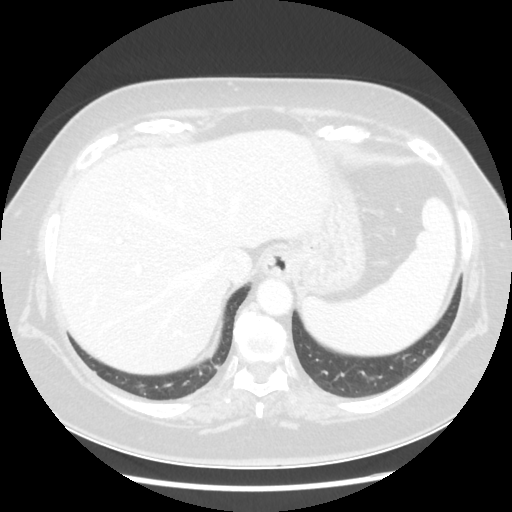

Reconstructed NATIVE CT scan (cycle consistency)

Full window (WL 1023.5, WW 4095 β†’ Low βˆ’1024, High +3071)

Lung window (WL -600, WW 1500 β†’ Low βˆ’1350, High +150)

Mediastinum window (WL 40, WW 400 β†’ Low βˆ’160, High +240)